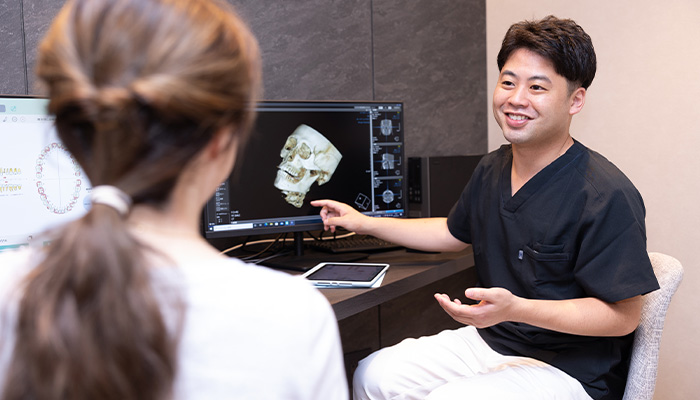

歯の治療に際し、不安に思っていることやお悩みになっていることをできるだけ伺ます。「○○が食べられるようになりたい」「歯を見せて笑えるようになりたい」「できるだけ歯を削らずに治したい」「長く自分の歯で噛めるようにしたい」「○月までは仕事が忙しくないので、一気に治したい」など、ご希望に応じて治療プランを立てて進めていきます。

歯の治療に際し、不安に思っていることやお悩みになっていることをできるだけ伺ます。「○○が食べられるようになりたい」「歯を見せて笑えるようになりたい」「できるだけ歯を削らずに治したい」「長く自分の歯で噛めるようにしたい」「○月までは仕事が忙しくないので、一気に治したい」など、ご希望に応じて治療プランを立てて進めていきます。

自然な笑顔の状態での歯の見え方を調べるために、当院では動画を撮影しています。笑顔の瞬間を切り取る写真撮影に比べると、動画の方がより正確に治療ゴールをシミュレーションできるようになります。

CT撮影をせずに矯正をすると、骨から歯が飛び出して、歯茎が下がる、歯の神経が死んでしまう、などのトラブルが起こります。矯正開始前にCT撮影をしない病院はまだまだ多いため注意が必要です。